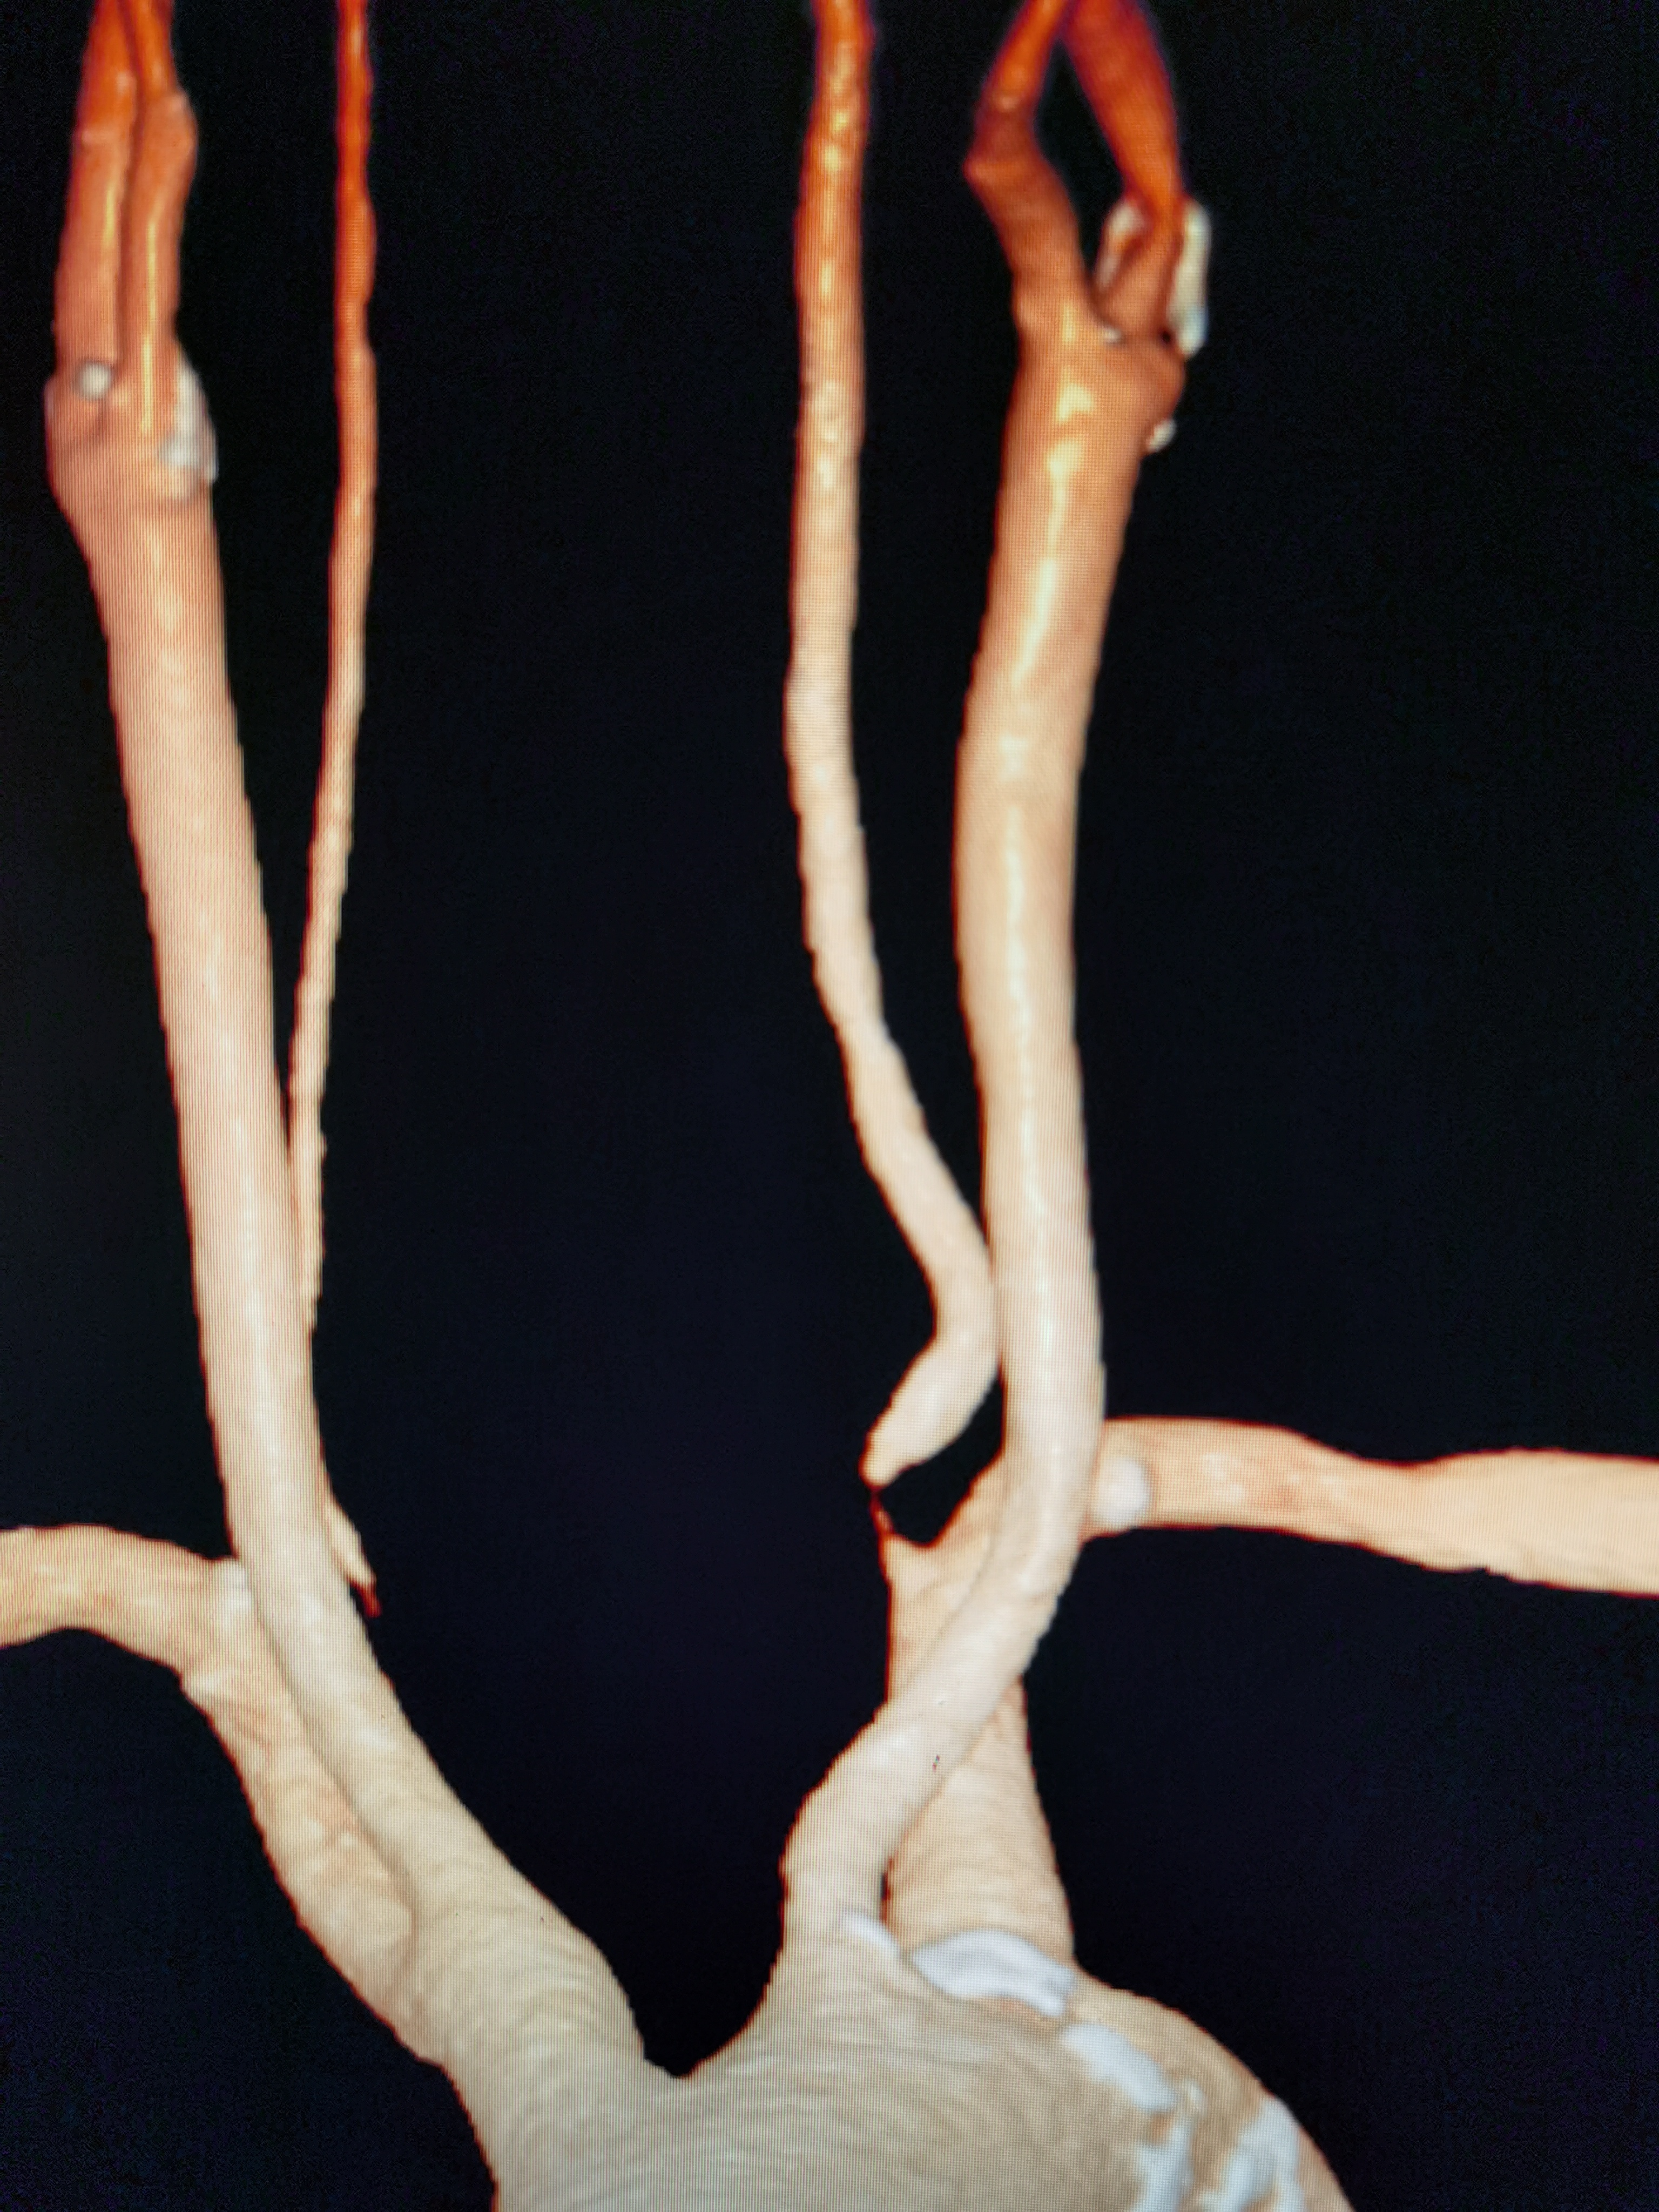

椎動脈閉塞3個月,介入開通

治療前患者男性,41歲,既往高血壓、高脂血癥病史,有吸煙及飲酒史?;颊?月前出現(xiàn)枕葉和小腦梗塞,1月前在當?shù)匦蠨SA發(fā)現(xiàn)左側椎動脈V1-V2(至C5水平)閉塞,枕動脈肌支自V3供血,并向近心端返流至C5水平,呈震蕩血流,考慮梗塞是由于震蕩血流造成椎動脈內斑塊脫落引起,患者存在罕見的椎動脈殘腔綜合征(VertebralArteryStumpSyndrome,VASS),這是后循環(huán)缺血性卒中的少見原因。治療中治療方案:因椎動脈起始端閉塞過長,故設計手術方案為頸外動脈-橈動脈-椎動脈搭橋(ECA-RA-VAbypass),術中行腦氧、TCD和電生理監(jiān)護等多模態(tài)監(jiān)護。該患者情況因為既往放置主動脈內覆膜支架無法行介入微創(chuàng)治療。治療后治療后1年術后腦灌注CT對比術前改善,術后患者訴視物光線較術前明亮清晰,術后一年復查搭橋血管通暢良好。